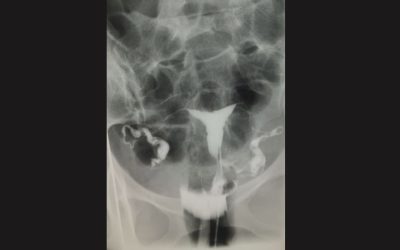

Hystérographie

L’hystérographie est un examen radiographique (utilisant des rayons X) permettant d’explorer la cavité et les trompes utérines.